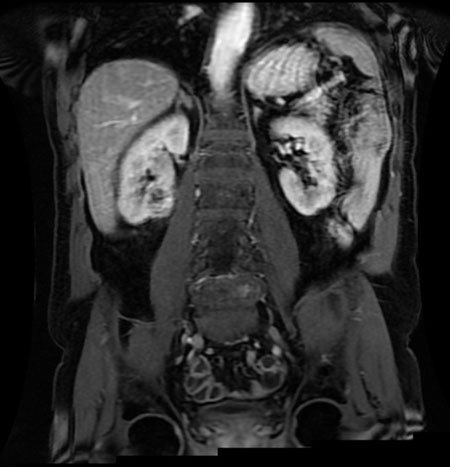

Systemic amyloidosis causing profound retroperitoneal and perinephric calcified deposits

Keywords: Amyloidosis, Lymphoplasmacytic lymphoma, Retroperitoneal calcifications, Systemic amyloidosis